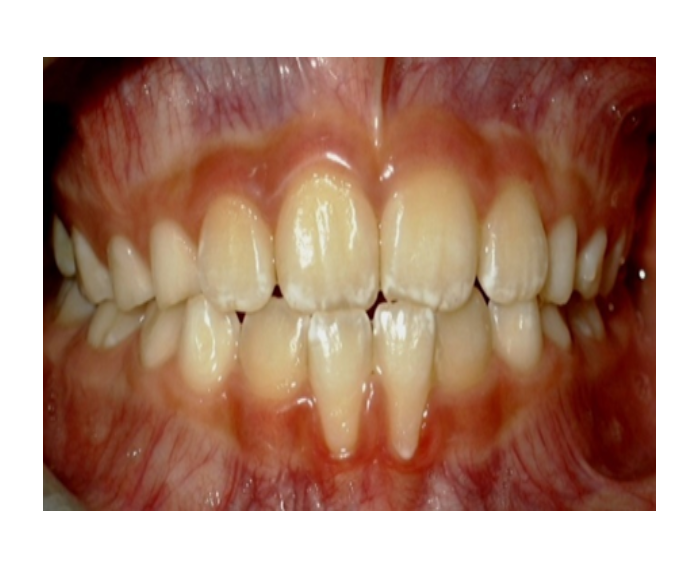

Mordida cruzada posterior bilateral